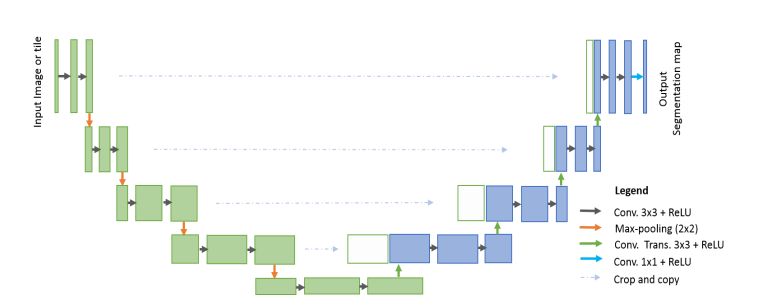

unet

U-Net 是一种经典的用于医学图像分割的卷积神经网络(CNN)架构。它的设计初衷是为了解决医学图像中复杂目标(如肿瘤、器官等)的精确分割问题。U-Net 通过对称的编码器和解码器结构,结合跳跃连接(skip connections),实现了在分割任务中高效的特征提取和精细的空间恢复。

U-Net 的网络结构分为两个主要部分:编码器(下采样部分)和解码器(上采样部分)。编码器部分通常由一系列卷积层和池化层组成,目的是逐步提取图像中的抽象特征并降低空间分辨率。每个卷积层后面跟随一个非线性激活函数(通常是ReLU),用于增强模型的非线性表达能力。池化层(如最大池化)则用于降低空间分辨率并减少计算量。

解码器部分通过上采样逐步恢复图像的空间分辨率。上采样通常通过反卷积层(或转置卷积)实现,目的是将低分辨率的特征图恢复到原始图像的尺寸。解码器中的关键设计是跳跃连接,具体来说,U-Net 会将编码器各层提取的特征图直接传递到解码器对应层进行融合。这种跳跃连接保证了解码器能够使用来自编码器的高分辨率特征,帮助恢复图像的细节,特别是在分割物体的边界部分。

最终,U-Net 使用一个 1x1 的卷积层将解码器的输出映射到所需的分割类别数,生成像素级的分割结果。为了获得更精确的分割结果,输出通常通过一个 Sigmoid(用于二分类)或 Softmax(用于多分类)激活函数进行处理。

U-Net 的优势在于它能够在进行高效特征提取的同时,保留图像中的细节信息,尤其适用于需要精确分割边界的医学图像。通过跳跃连接,U-Net 可以有效地融合来自浅层和深层的特征,使得模型既能捕捉图像的全局语义信息,又不丢失细粒度的局部信息。这使得 U-Net 成为了医学图像分割领域中最常用的深度学习架构之一。